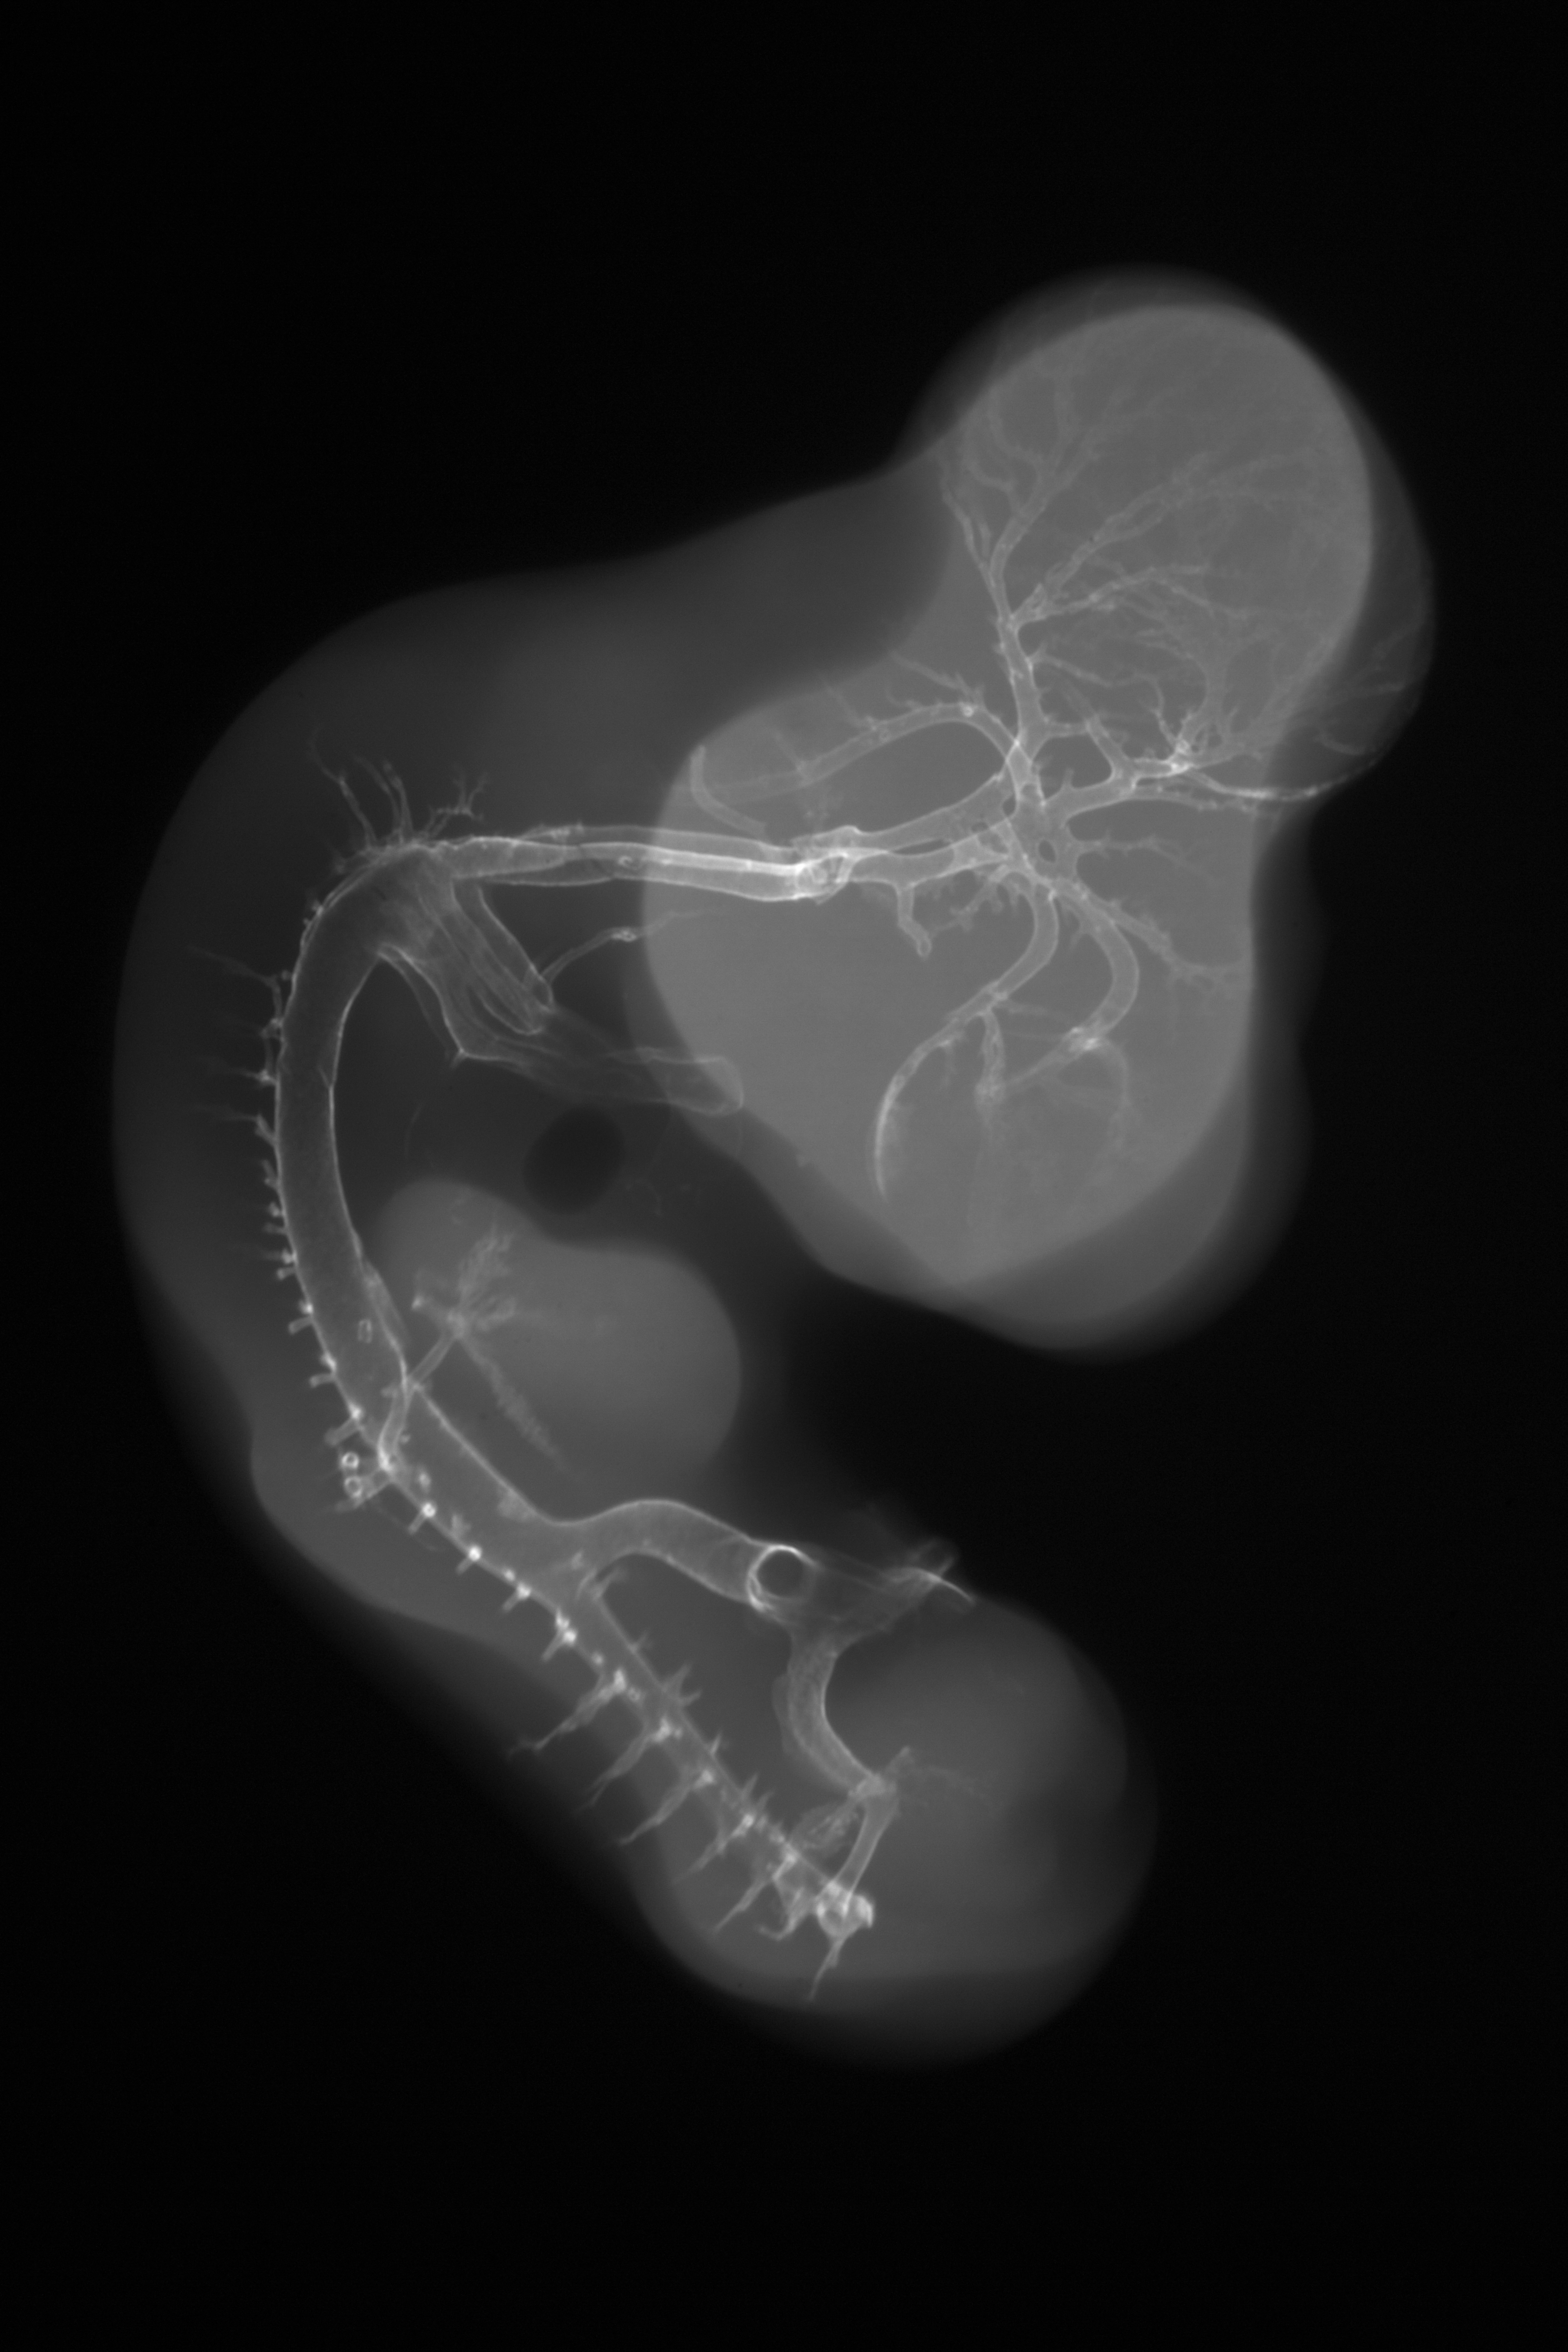

Chick Embryo Microangiography

Hamburger-Hamilton (HH) Stage 26 (approx. 5 days)

X-Ray Micrographs